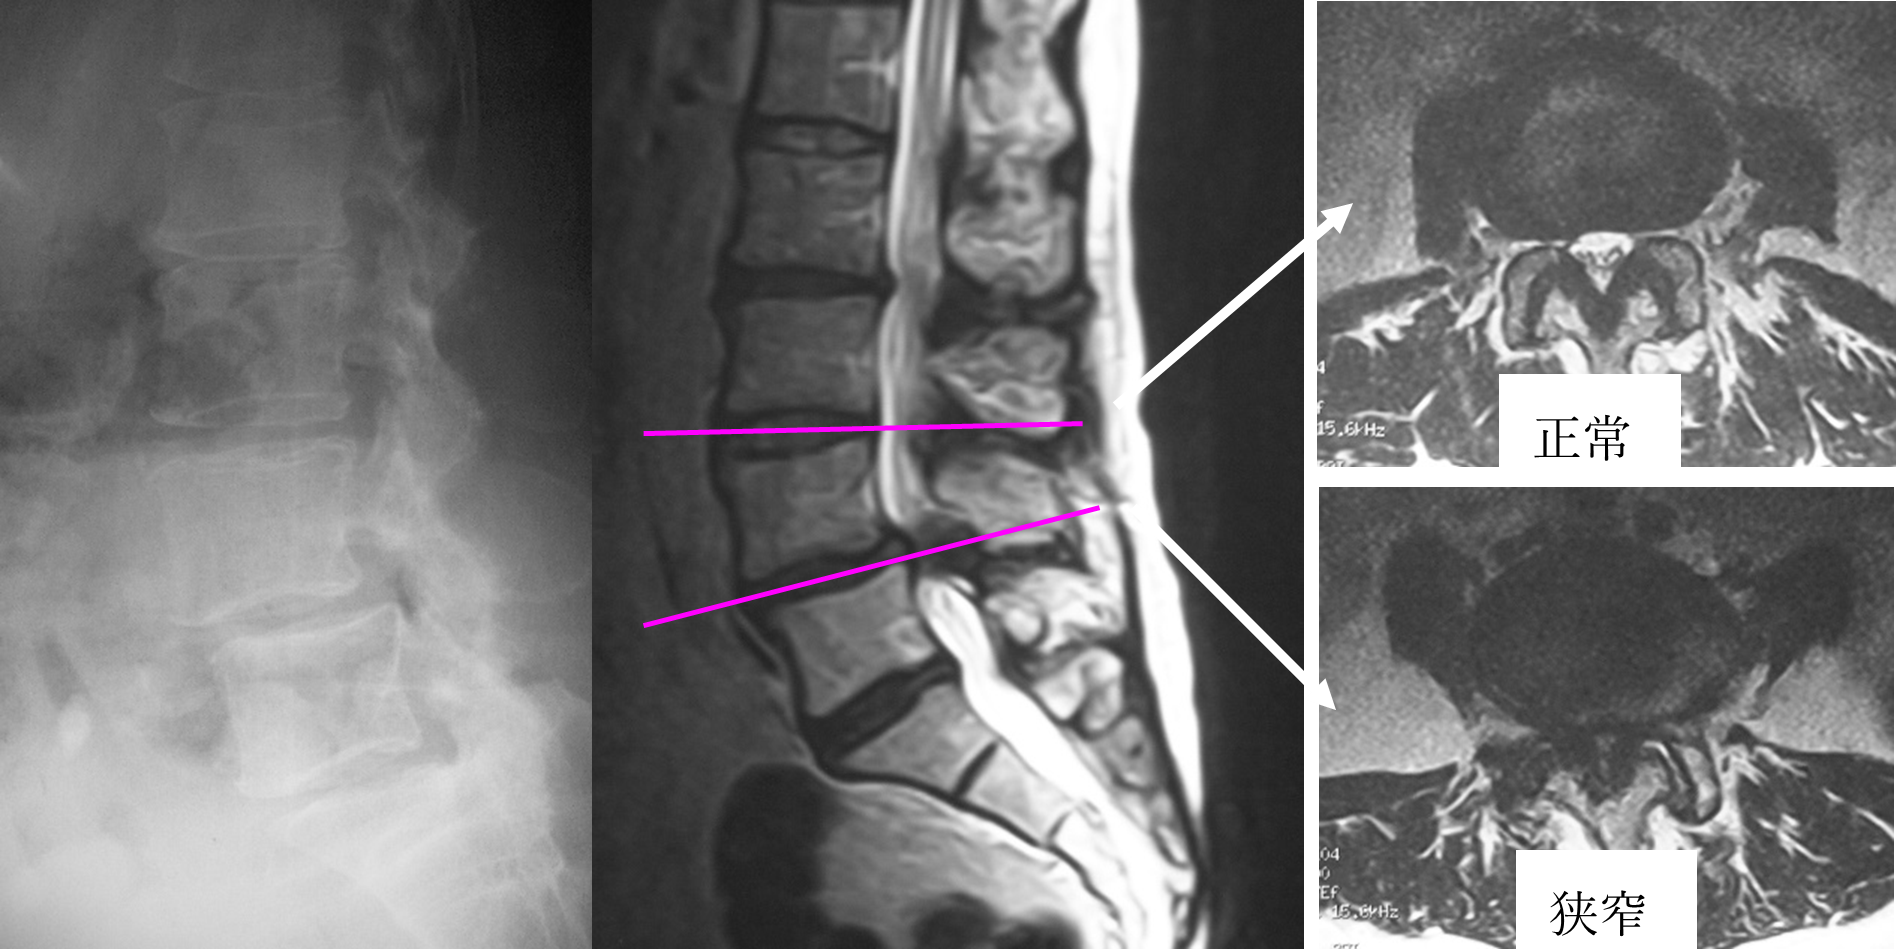

腰椎変性すべり症は、腰の骨がずれてしまう病態で、第4番目の腰椎に多く認められます。加齢とともに椎間板や関節・靭帯がゆるみ、腰椎が不安定性(ぐらつき)を伴ってずれるようになります。骨のずれによって神経の通り道である脊柱管が挟くなり、下肢の痛みやしびれなどが生じます。

間欠跛行(長い距離を歩くと痛み・しびれが強くなり、しゃがみこむと症状が軽減する)や、末期になると安静時にも下肢の痛みやしびれが出現するようになります。動的要因(腰の骨の動き)も大きく関与するため、ときにMRIでも顕著な所見が現れないことがあり、注意が必要です。治療は、まず薬物治療やコルセットなどの保存治療を行い、下肢の疼痛やしびれが強い場合は、神経ブロックなどを試みます。保存治療では改善が乏しい場合、下肢の麻痺や排尿障害などの重度の神経障害を認めた場合などには手術治療を考慮します。手術は主に除圧術と固定術があります。除圧術は、ずれた腰の骨の一部を削り脊柱管を解放する方法で、不安定性が著明でない場合や、内科的な併存症を有する患者様、あるいはご高齢の患者様などで手術のリスクが高い場合などに選択します。固定術は、すべりをある程度戻した状態で、人工スペーサーや金属製のスクリューにより脊椎を固定し安定化させます。石井医師は、まず十分に手術の適応を判断し、手術が必要な場合にはできるだけ最小侵襲(低侵襲)手術を取り入れ、術後早期にリハビリテーションを開始し、早期社会復帰を目指しています。腰椎変性すべり症の最小侵襲手術として、最小侵襲椎弓切除術、MIS-TLIF、LIF、CBTなどの手術方法があります。